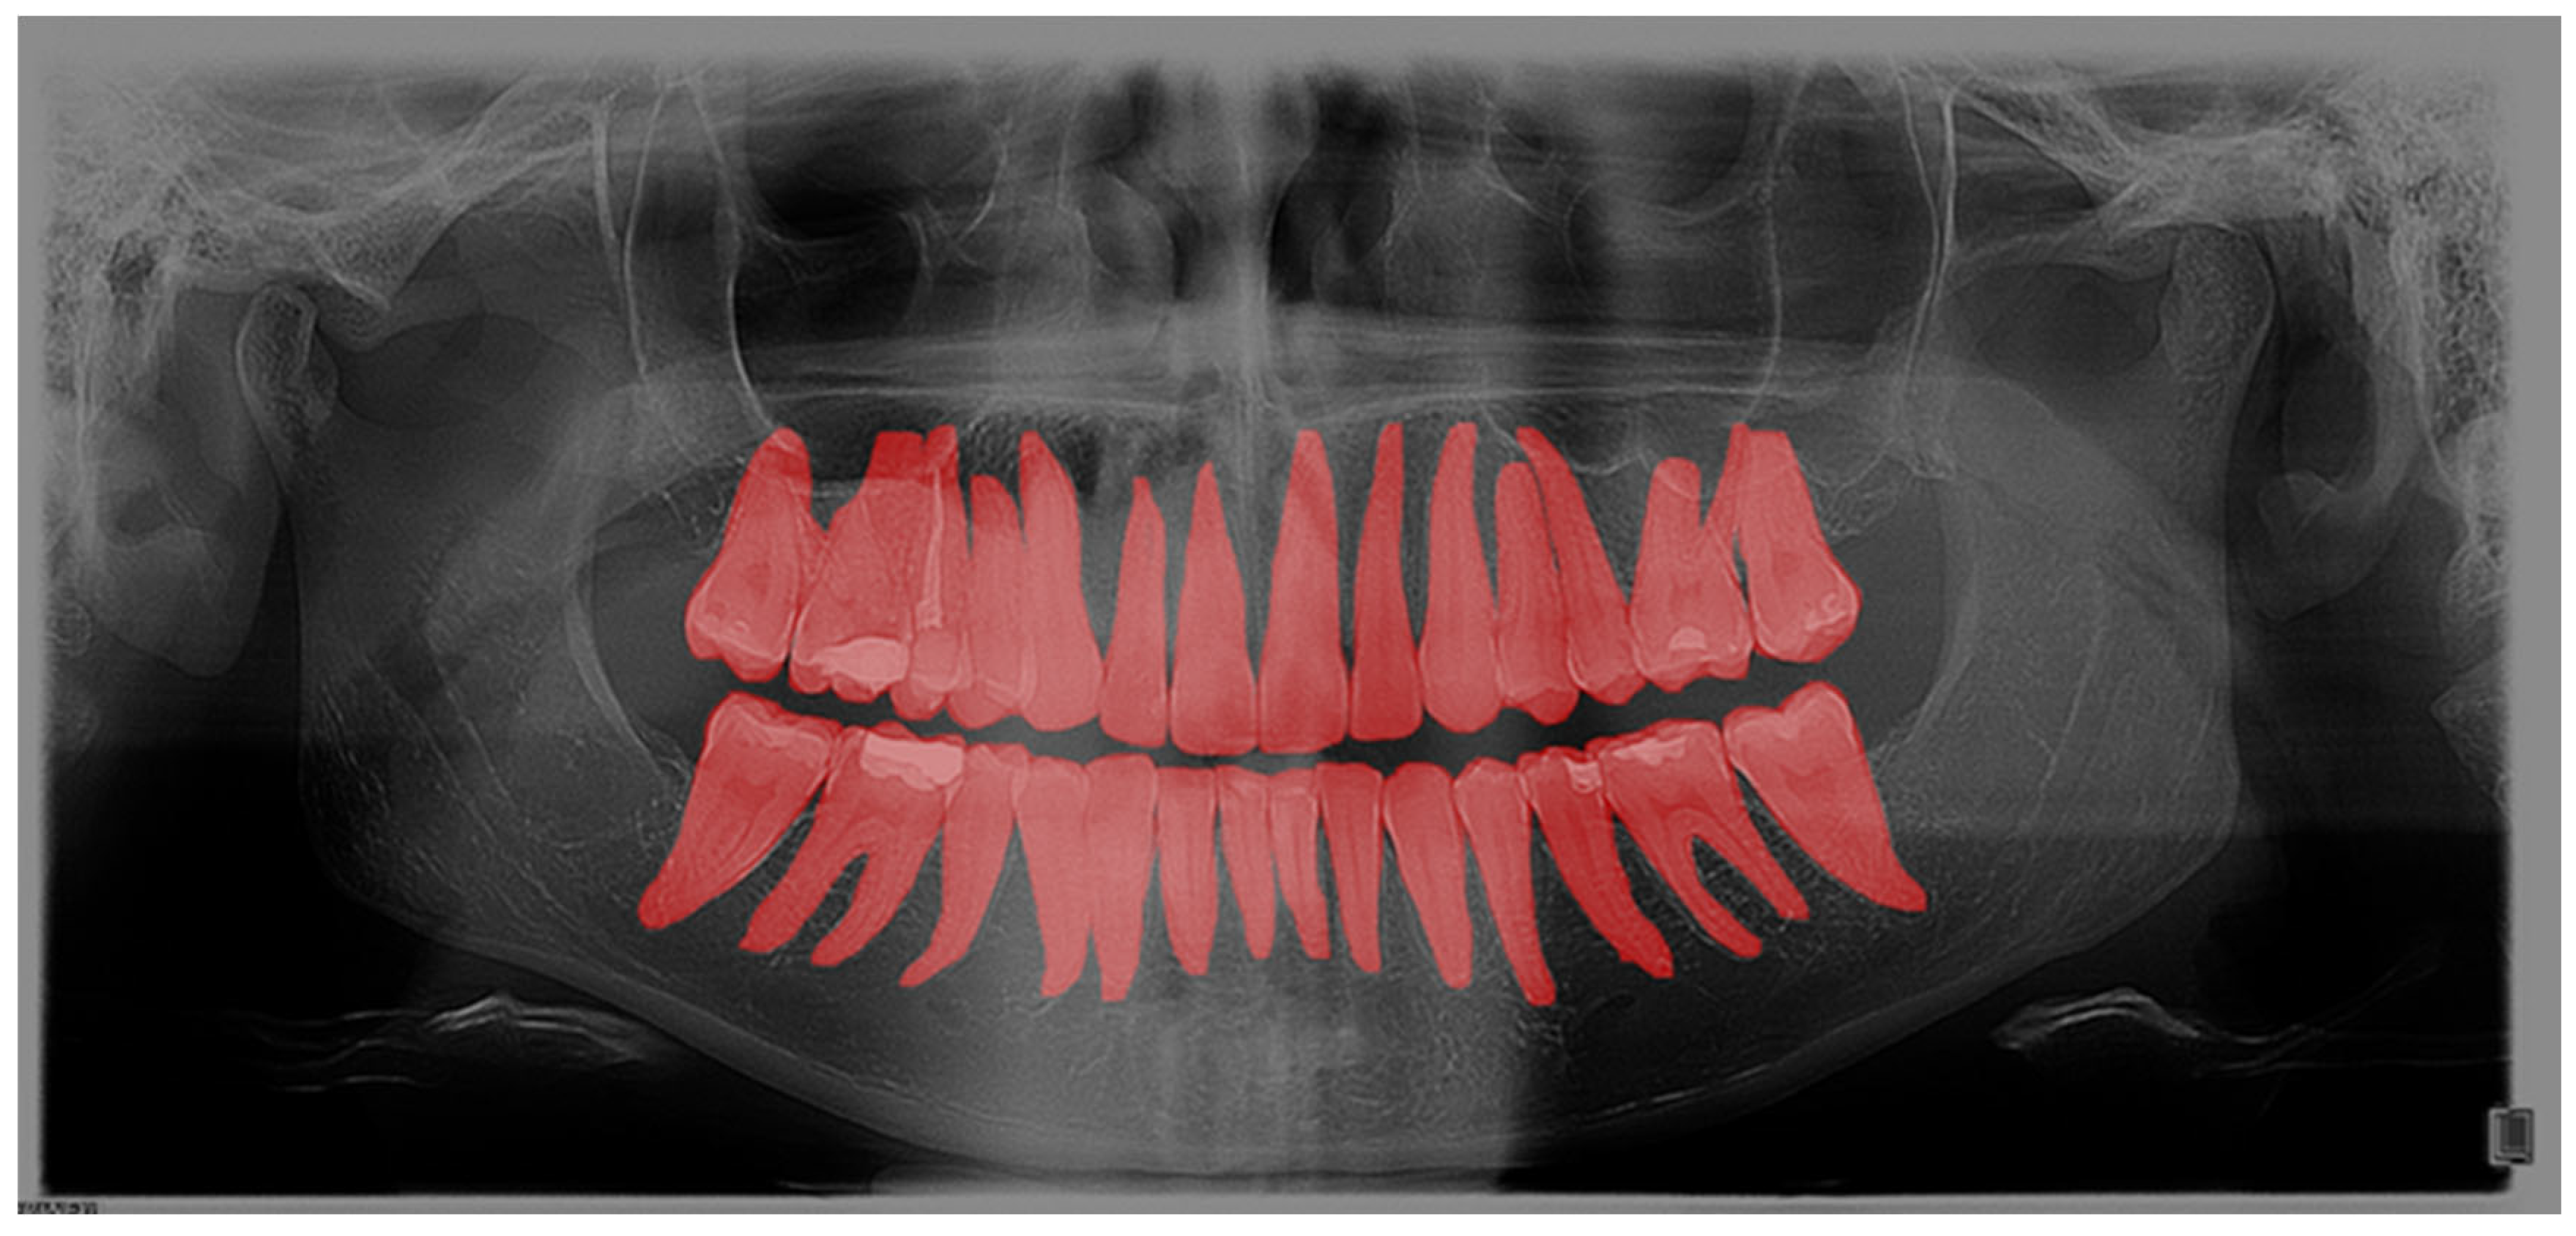

The computer program GIMP 2.10.22 was used to process the OPGs. GIMP is a powerful, free, and open-source image editor. The tool’s editing capabilities provided the annotators with a robust toolbox to adjust image parameters, helping them better discern the boundaries of the target regions. Importantly, the original OPGs were not modified during this process; everything except the annotated masks was discarded. Additionally, GIMP’s open format facilitated easy handling of per-pixel annotation data. Regarding annotation speed and validation, marking an entire tooth took about 10 min, while segmentation time depends on the number of interventions the tooth has undergone. For validation, we conducted multiple rounds of annotation-review iterations. Annotations were saved as XML files in the PASCAL VOC format for further use in neural networks. Every annotation step was conducted manually by a human expert; no annotations were automatically generated. Within the program, each tooth was outlined, covering the entire range of the tooth, including the crown and root (Figure 1). Teeth were labelled using the dual or binary system (FDI).

As a second layer, after outlining the teeth, each filling, crown, bridge, implant, endodontic filling, and tooth build-up was marked (Figure 2).

Figure 2. Segmentation of dental interventions on OPG in the GIMP program.